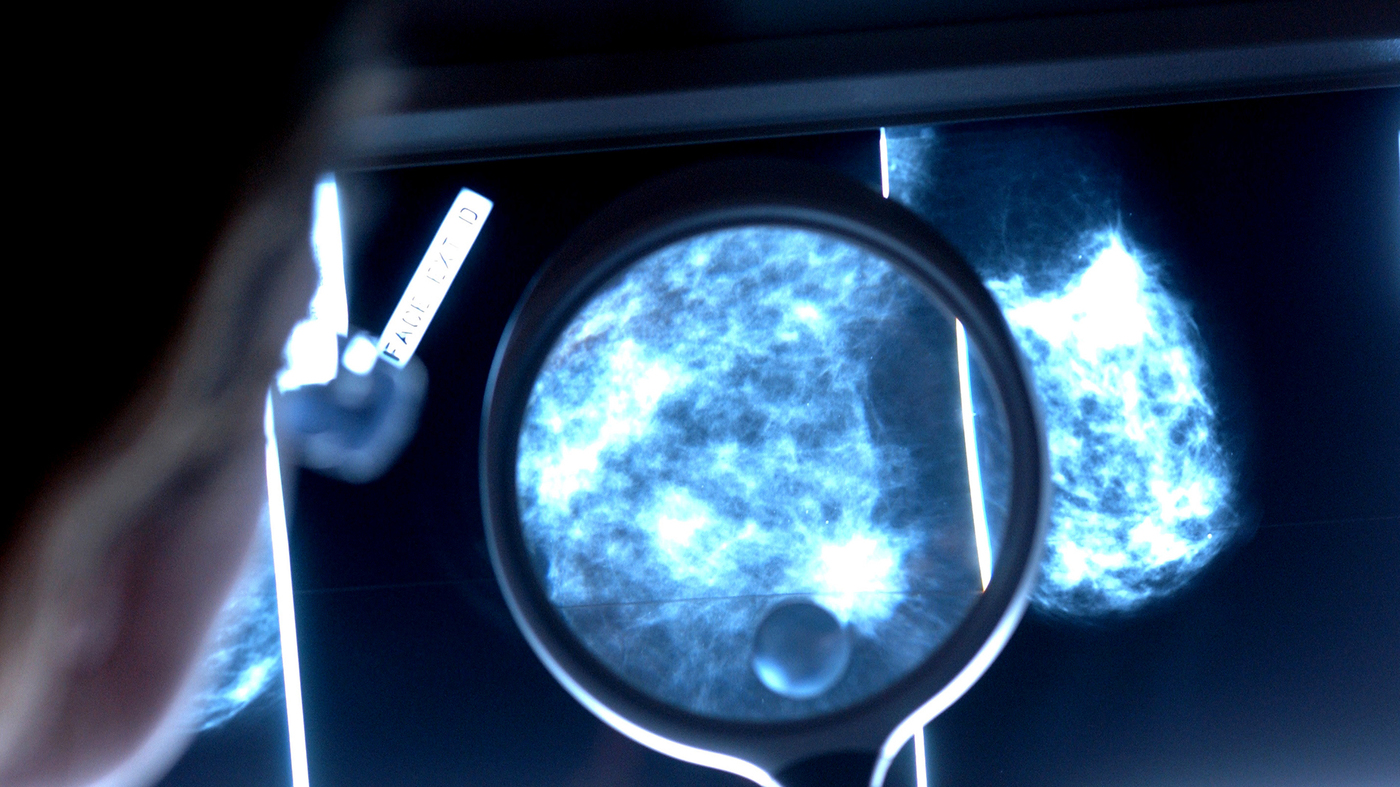

Annual Mammograms Could Save 1000s of Lives

How frequently should women get a mammogram? Guidelines differ, but a new study estimates thousands of US lives could be saved if mammograms were done every year from age 40 to 84.

Hendrick and his colleagues used computer modeling to assess the three major mammogram recommendations: annual screening from age 40 to 84; annual screening at ages 45 to 54, then every other year from 55 to 79; or every other year from 50 to 74.

Deaths from breast cancer would fall by an average of 40% with annual screenings from 40 to 84, the investigators reported.

By comparison, breast cancer mortality would decline 31% with screening until age 79. And it would drop 23% with every-other-year mammography from 50 to 74, which is recommended by the US Preventive Services Task Force.

The number of lives saved from breast cancer would be about 29,400 with annual screening from age 40 to 84; and about 22,800 and 17,200, respectively, for the other two recommendations, the researchers found.